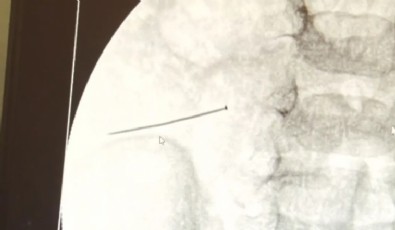

Burada yapılan tetkiklerde 2 yaşındaki çocuğun ince bağırsağında yaklaşık 3 santimlik toplu iğne olduğu ve bağırsağı deldiği belirlendi.

Ertesi gün bağırsakta delinmeyle sonuçlanmış ve çocukta da ciddi semptomlar meydana getirmişti. Bu şekilde hasta bize başvurdu. Tetkikler sonucunda yabancı cismi tespit ettik, semptomları ve bulgularına göre de çocuğu ameliyata aldık. Yaklaşık 3 santim boyunda bir toplu iğnenin ince bağırsağı deldiğini, ince bağırsaktaki içeriğin de karın içerisine dolduğunu gördük. Ameliyatı başarılı bir şekilde tamamladık, yaklaşık 1 saat süren bir ameliyattı' dedi.

Öte yandan, yaklaşık 3 santimlik toplu iğne filme yansıyan görüntüsüyle gözler önüne serildi.